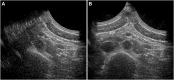

Introduction: In this paper we introduce in vivo multi-aperture ultrasound imaging and elastography of the abdominal aorta. Monitoring of the geometry and growth of abdominal aortic aneurysms (AAA) is paramount for risk stratification and intervention planning. However, such an assessment is limited by the lateral lumen-wall contrast and resolution of conventional ultrasound. Here, an in vivo dual-aperture bistatic imaging approach is shown to improve abdominal ultrasound and strain imaging quality significantly. By scanning the aorta from different directions, a larger part of the vessel circumference can be visualized. Methods: In this first-in-man volunteer study, the performance of multi-aperture ultrasound imaging and elastography of the abdominal aortic wall was assessed in 20 healthy volunteers. Dual-probe acquisition was performed in which two curved array transducers were aligned in the same imaging plane. The transducers alternately transmit and both probes receive simultaneously on each transmit event, which allows for the reconstruction of four ultrasound signals. Automatic probe localization was achieved by optimizing the coherence of the trans-probe data, using a gradient descent algorithm. Speckle-tracking was performed on the four individual bistatic signals, after which the respective axial displacements were compounded and strains were calculated. Results: Using bistatic multi-aperture ultrasound imaging, the image quality of the ultrasound images, i.e., the angular coverage of the wall, was improved which enables accurate estimation of local motion dynamics and strain in the abdominal aortic wall. The motion tracking error was reduced from 1.3 mm ± 0.63 mm to 0.16 mm ± 0.076 mm, which increased the circumferential elastographic signal-to-noise ratio (SNRe) by 12.3 dB ± 8.3 dB on average, revealing more accurate and homogeneous strain estimates compared to single-perspective ultrasound. Conclusion: Multi-aperture ultrasound imaging and elastography is feasible in vivo and can provide the clinician with vital information about the anatomical and mechanical state of AAAs in the future.